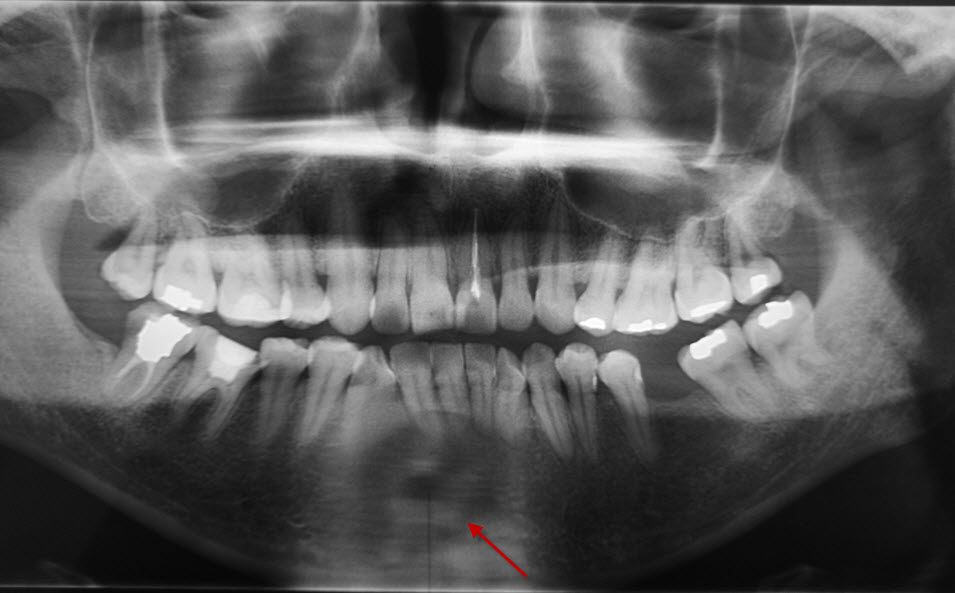

CT53187:请帮忙看看这个口腔全景CT 片(3.22新增了CT片)

病人是一年前发现右下颌有肿块,但是当时拍口腔片没有发现问题,个人也没有感觉,于是随访,这次复查,请问各位老师。箭头处怎么诊断? 并且对比一年前的片子,发现牙齿有移位。 ...

下颌骨切牙根尖处可见团块状低密度占位,内见稍高密度影。考虑:下颌骨根尖囊肿并感染可能。建议CT检查。

根尖脓肿?建议行CT检查。